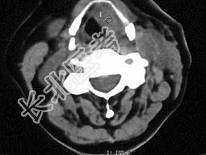

- 单项选择题女,54岁, 鼻咽部异物感约3个月,PE: 左侧声带固定,可见肿物, CT如图所示,应诊断为 ( )

B、喉癌